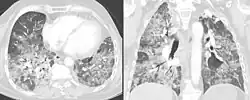

Tomografia axial e coronal.

O diagnóstico é baseado na história de sintomas após a exposição ao alérgeno e em testes clínicos. Exames de sangue indicam sinais de inflamação pouco específicos, a radiografia de tórax revela áreas de opacidade difusa, pode haver edema e fibrose, e testes de função pulmonar revelam doença pulmonar restritiva.[6]